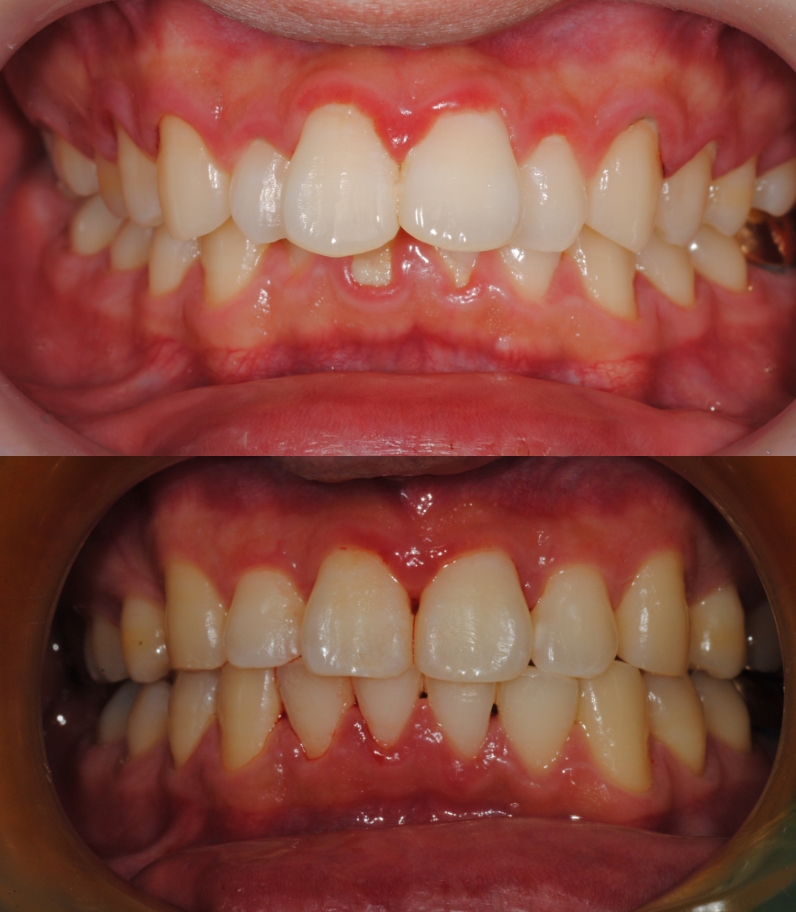

치아교정 전/후

실제 케이스

소아 교정부터 성인 교정까지 환자분들의

상황과 상태에 맞는

올바른 치료를 위해

끊임 없이 연구하고 고민합니다.

치아교정

치료기간 : 2023.05 - 2023.12 (7개월)